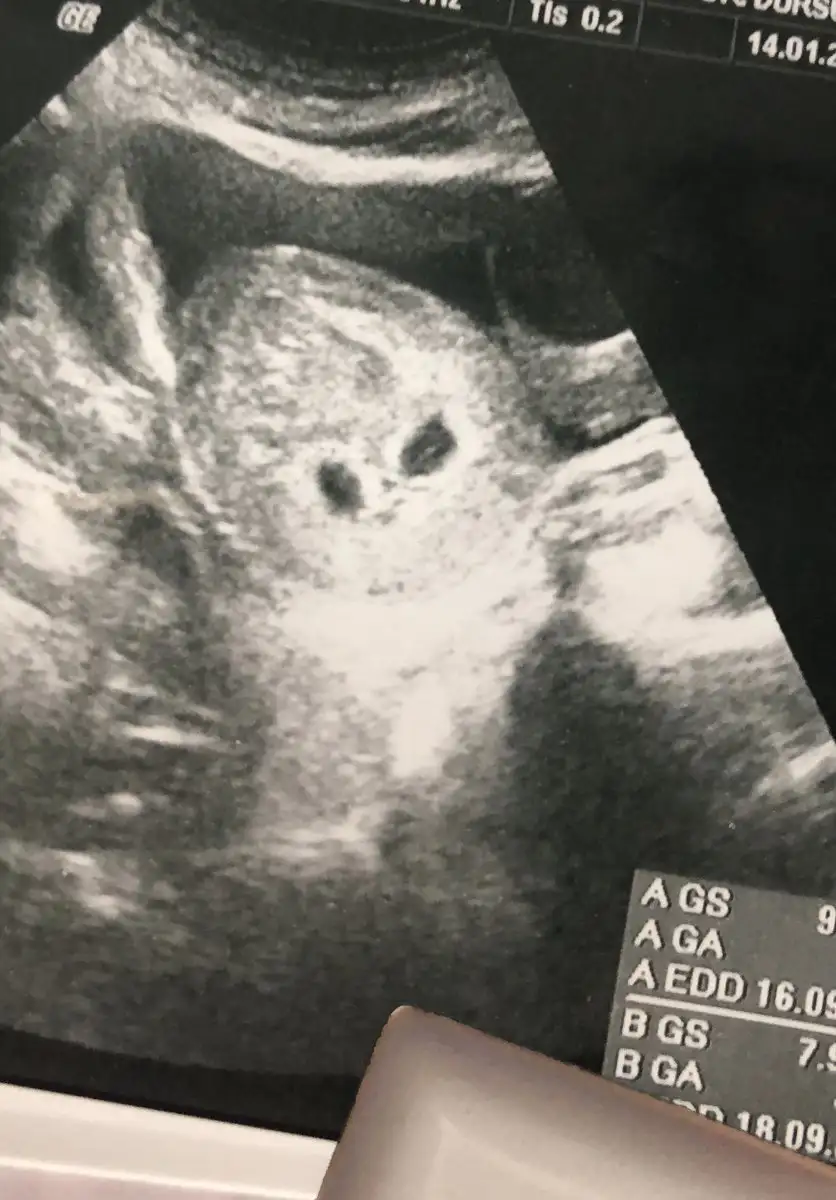

Benimde ikiz biri 5haftalık biri 4+5 yani iki gün geriden geliyo büyük olan 9.86 küçük olan 7.98